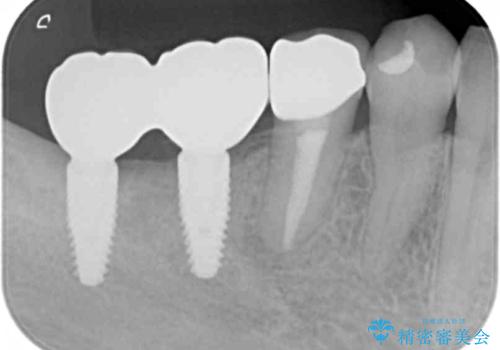

インプラント治療による咬合機能回復

インプラントは高い確率で骨に結合し、しっかりとした咬合力を回復することができます。

長年安心してしっかりと噛んでいただけるよう今回は骨を増成する治療計画としました。